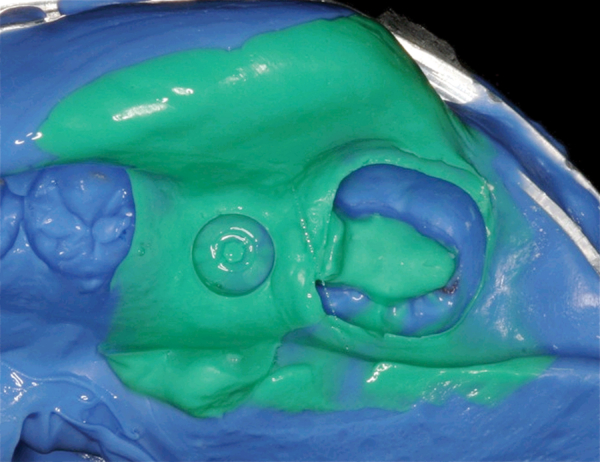

For larger, more complicated, multi-unit cases, the aforementioned technique must be adhered to without question. However, single crown or two adjacent crowns cases have been successfully restored using a dual-arch impression technique for many years. This technique provides the laboratory with a quadrant impression of the prepared arch, a bite registration, and a highly accurate quadrant impression of the opposing arch – all in one stable combined impression. Obviously, the practitioner must exercise caution as to which indirect cases are suitable to this technique. For instance, the number of units involved should not exceed two adjacent crowns, although some rare cases of small three-unit bridges may be suitable for the dual-arch impression technique. Additionally, the crown should not be on the terminal tooth of the arch as the goal is to still provide the laboratory with as much information as possible to ensure a proper fitting and functioning restoration. This includes the impact that the patient’s occlusion can have on the case.

While the dual-arch impression technique is a simplified version of the articulated full-arch tray technique, there are pitfalls to avoid in each of its steps. The incorrect choice of tray, as well as tray material and/or light body, can all have a negative impact on the final impression and consequently, the final restoration.

The tray material chosen for the dual-arch technique is also vital for providing the laboratory with a stable, accurate impression. Dual-arch impressions differ from full-arch impressions in that a great deal of dimensional stability of the impression depends on the rigidity or hardness of the tray material versus the metal or plastic full-arch tray. The best choice would be a tray material designed to be both as rigid as possible, yet displaying the ideal flow that does not displace the light body from the preparation. For optimal dimensional stability, ensure that the upper and lower aspects of the tray material are actually connected buccal and lingually.